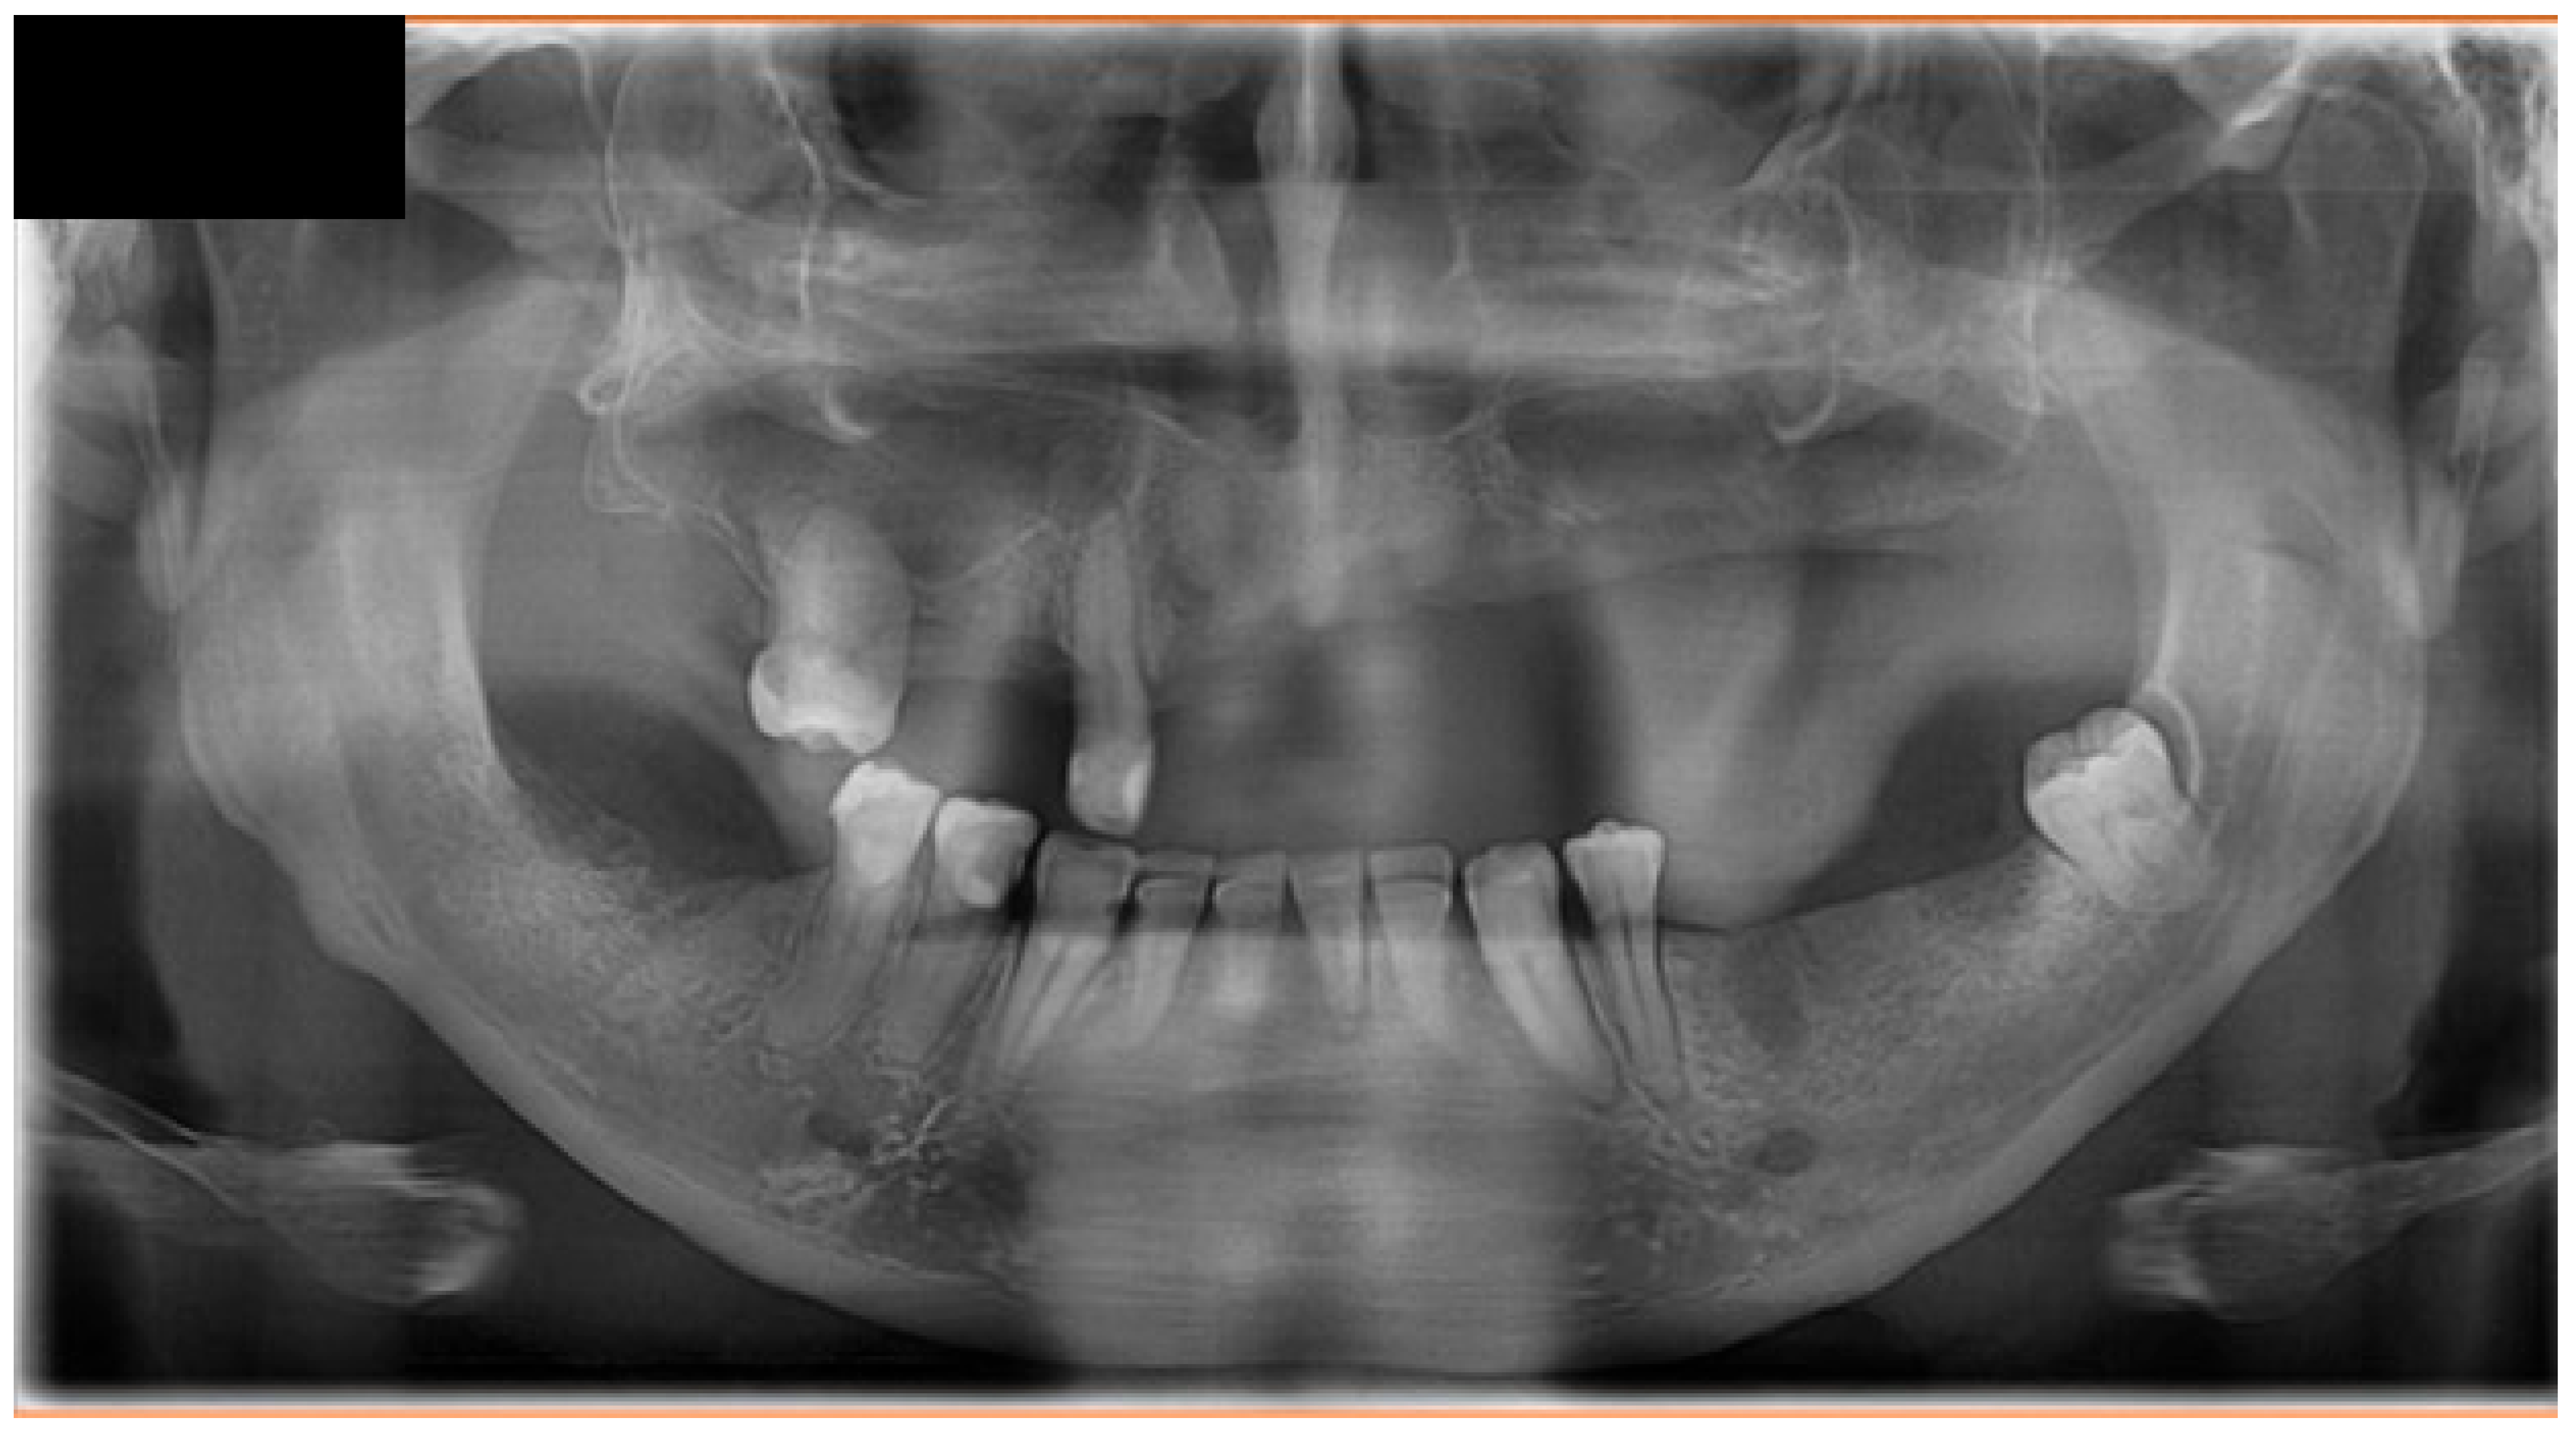

Conservative dental therapy was prioritized whenever feasible. Periodontal treatment, focal dental sanitation, and correction of the sharp alveolar ridge using a piezoelectric spherical tip were performed under antibiotic coverage during multimodal oncologic treatment.

Combined multimodal therapy resulted in a marked initial clinical improvement. During SMILE chemotherapy (weeks 6–10 from initial presentation), significant regression of the oral lesion was observed, accompanied by symptomatic relief (Figure 5 and Figure 6). Following completion of 3D-conformal radiotherapy to a total dose of 50 Gy (month 4), PET-CT demonstrated a partial metabolic and morphological response, consistent with temporary disease control. After a follow-up period of approximately three months (months 5–7) following completion of radiotherapy, the patient remained clinically stable, with no evidence of local progression. However, at approximately nine months from initial presentation, PET-CT revealed extensive systemic relapse, involving nodal, pulmonary, adrenal, cutaneous, and subcutaneous sites (Figure 7).

Figure 6. Digital orthopantomogram (DOP) obtained during clinical remission, demonstrating stabilization of maxillary structures following combined oncologic treatment and supportive dental management.